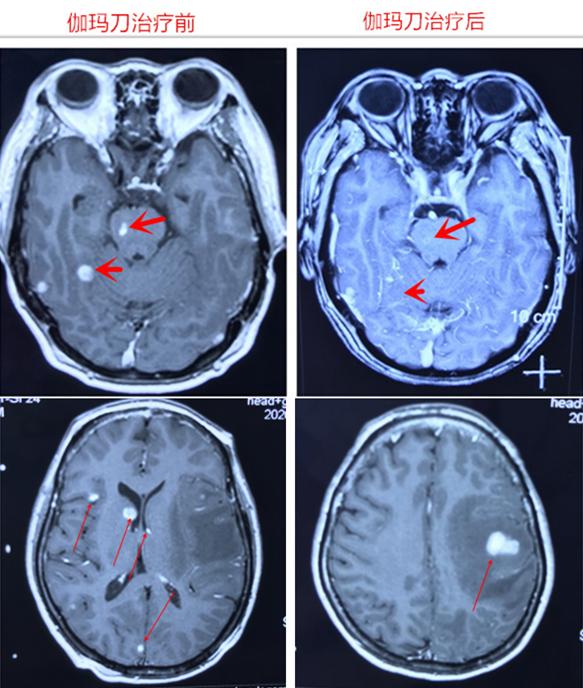

患者53岁,女性,今年年初因右侧肢体活动不灵活3天入院治疗,胸部、上腹部CT平扫+增强提示:左肺下叶背段占位,肝右叶多枚片状病灶,倾向于转移瘤;头颅MRI平扫+增强提示:颅脑多发异常信号:考虑诊断:1.颅内多发转移瘤 2.肺癌 3.肝内转移瘤。

详细告知患者家属目前病情:病灶位于脑干,颅内多发,外科手术难以全切除,手术风险大,可能引起瘫痪昏迷,经过多科室会诊讨论,认为伽玛刀精确放射治疗颅内多发转移瘤效果更好。在征得患者及家属同意后,表示同意伽玛刀治疗,完善入院治疗前检查后,以左额、顶、颞叶、右侧基底节区、颞叶及脑干共6处病灶为本次治疗靶区,伽玛刀治疗后2月随访脑干病灶消失,其他病灶明显缩小。